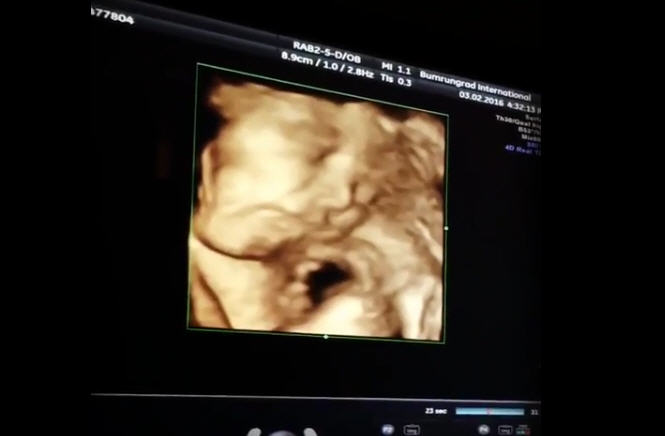

ต่าย ชุติมา สุดตื่นเต้น อวดคลิปอัลตราซาวด์ลูกน้อยในครรภ์ 8 เดือน ดิ้นดุกดิก จมูกโด่งมาก ส่งยิ้มให้คุณพ่อคุณแม่ด้วย

ใกล้ถึงกำหนดคลอดเข้ามาทุกที เตรียมพร้อมเต็มที่มากกับการเป็นคุณพ่อคุณแม่ สำหรับสาว ต่าย ชุติมา และสามีหนุ่มนักธุรกิจ ทิม พิธา ที่ล่าสุด (10 กุมภาพันธ์ 2559) สาวต่าย ได้อวดคลิปวิดีโออัลตราซาวด์ลูกครั้งแรกแบบ 4D ในอายุครรภ์ 8 เดือน ให้ได้ชมกันชัด ๆ

งานนี้ขอบอกเลยว่า คุณแม่ต่าย คุณพ่อทิม ตื่นเต้นกันสุด ๆ ที่อัลตราซาวด์เห็นลูกน้อยกำลังดิ้นดุกดิกในท้อง แถมมีชอตส่งยิ้มให้คุณพ่อคุณแม่ ทำท่าปาดน้ำลายด้วย น่ารักจริง ๆ เลย

ภาพแรกกับลูกของ ต่าย ชุติมา ยิ้มใส่กล้องระหว่างถ่ายวิดีโอ